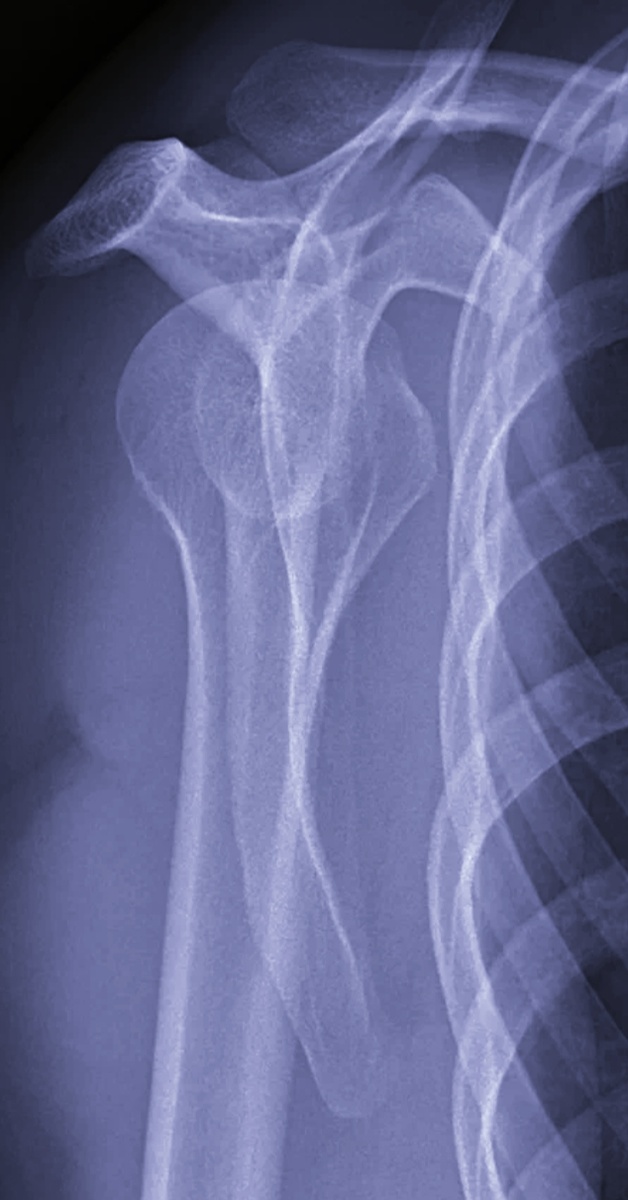

Женщина, 54 года на снимок плечевого сустава. Рука весит, как плеть.

-На вывих подозрение или травма была?-спросила я.

-Да не подозрение, а он и есть, не первый раз уже,-морщась от боли, сказала пациентка.

-Поди у вас , артропатия какая-нибудь?

-Она и есть, операцию предлагают, но я все не решусь, побаиваюсь.

-Часто у вас выпадает сустав?

–Раньше раз в год было, а в этот год я уже, наверное, раз третий, если не четвертый.

Понятное дело, чую, операцией и закончится. Не будешь же так лишний раз повернуться бояться.

-Ну, вставайте спиной к стойке, сделаем снимок.

-Все, обратно идите к травматологу, как вставят, на контроль придете...

-Да, знаю уже, хоть бы быстро вставили, а то в прошлый раз врач со мной измучился.

Ну, думаю, а как вы хотели? Это не очень просто и сил и знаний требует немеряно. У нас травматологи все крепкие и плечистые мужчины.

Пришли назад через тридцать минут, вместе с травматологом Виталием.

–Дайте, гляну сам,-попросил вспотевший врач. –Кое -как вставил.

-Так, она говорит, что у нее артропатия.

–Ну, я ей и поставил, уже год уговариваю.

–По моему, на месте, разве нет?

-Да, на месте, но еще раз и я не смогу вставить, операцию бы ей.

-Так приведите аргументы.

-Постараюсь.